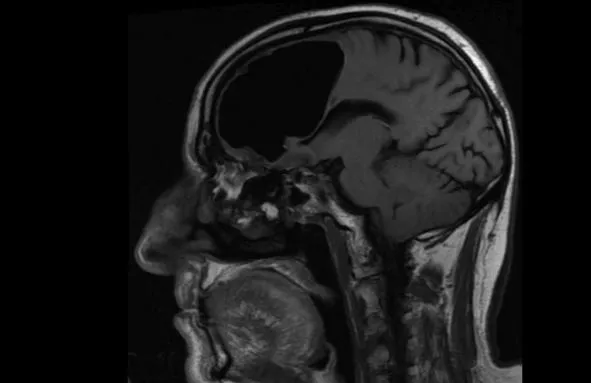

Phim chụp MRI cho thấy một phần não của ông cụ bỗng dưng biến mất kỳ lạ. Ảnh: BMJ Case Reports

Cuối cùng, họ cho ông chụp CT và MRI não và họ khá sốc khi phát hiện ra một sự việc khác kỳ lạ. Thùy não trái của ông lão hoàn toàn trống không.

Theo như những gì phim chụp MRI cho thấy túi khí này được hình thành như một khối u xương lành tính, hình thành trong xoang người và dần bị ăn mòn qua đáy hộp sọ. Sự hình thành và vị trí đặc biệt của khối u đã tạo nên hiệu ứng van một chiều dần dần tạo thành một khoang không khí bên trong hộp sọ.

Thời gian kéo dài, mỗi khi bệnh nhân ngửi, hắt hơi hay ho, đều khiến đẩy một lượng khí nhỏ vào xoang và ngày càng "nới rộng" khoang không khí bên trong não bệnh nhân và dần dà nó phát triển thành một khoang khá lớn như hiện nay.